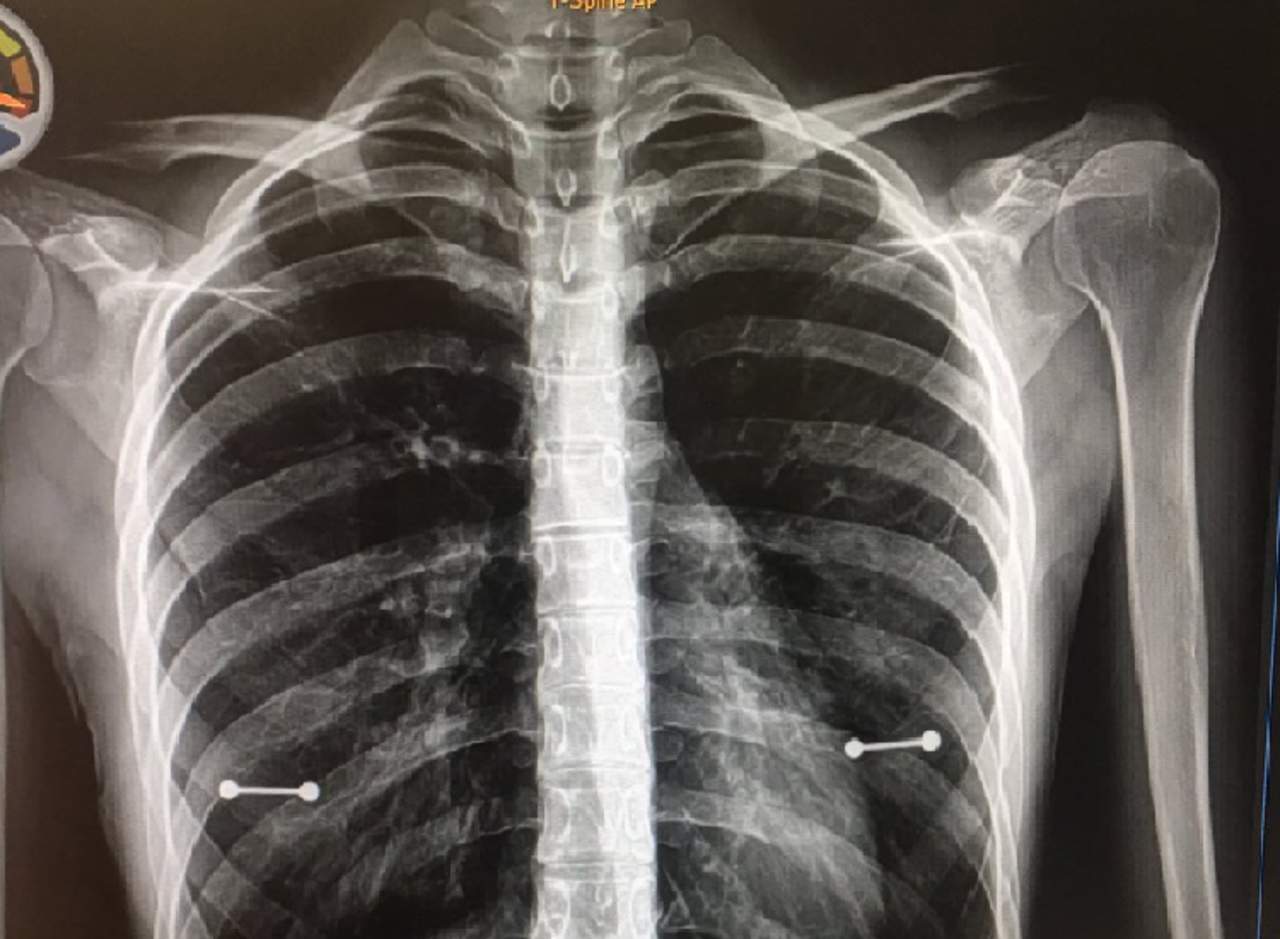

Se entera del secreto de su hija por unos rayos X

Una madre en Florida, Estados Unidos, se enteró de que su hija tiene piercings gracias a unas imágenes de rayos X.

La chica, Sydney Allen, de 20 años, padece siringomielia, un trastorno dentro de la médula espinal. Acudió con su madre a una revisión médica de rutina, donde la sacaron unos rayos X, que revelaron que Sydney tiene piercings en los pezones, informa el diario Mirror.

"Mi mamá vio mis piercings tan pronto como aparecieron los rayos X y el doctor y yo nos echamos a reír histéricamente. Estaba visiblemente molesta. Como no suelo quitarme la camisa, pensé que sería un secreto muy fácil de guardar”, confiesa la chica al sitio Buzzfeed.